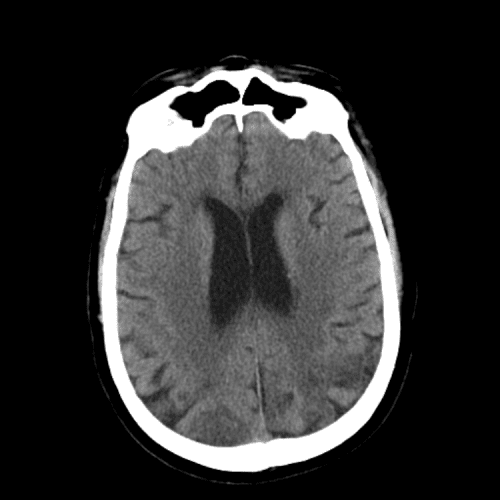

Basilar artery thrombosis